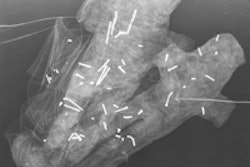

The researchers mapped coordinates for 48 skulls manually and compared the results with CT scan data. They found that eight coordinates on either side of the skull matched CT data, while five midline coordinates were less consistently accurate.